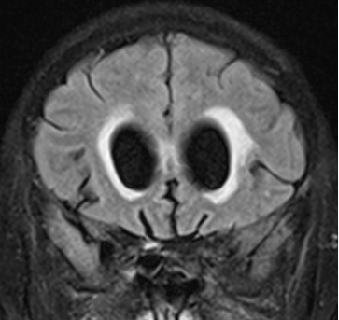

2015-12-13 MRI

2014-12-13